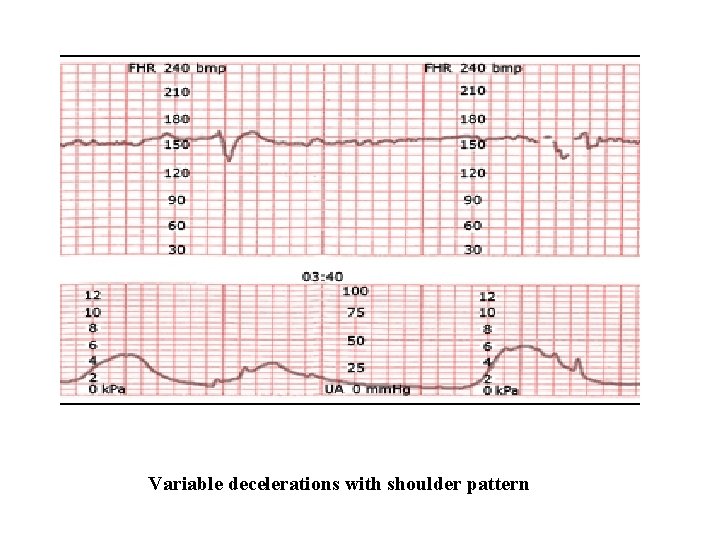

Variable Deceleration Abrupt decrease in FHR of > 15 beats per minute measured from the most recently determined baseline rate. The onset of deceleration to nadir is less than 30 seconds. The deceleration lasts > 15 seconds and less than 2 minutes. A shoulder, if present, is not included as part of the deceleration. Variable decelerations may be observed in up to 50% of NSTs. If nonrecurrent and <30 seconds, they are of no clinical significance.

Variable Deceleration Typical: • shoulders Atypical : • Overshoot • Loss of primary shoulder • Slow return to baseline (late component) • Baseline returns to a lower level(after deceleration) • Biphasic(W shape) • loss of variability during deceleration

Variable decelerations with shoulder pattern